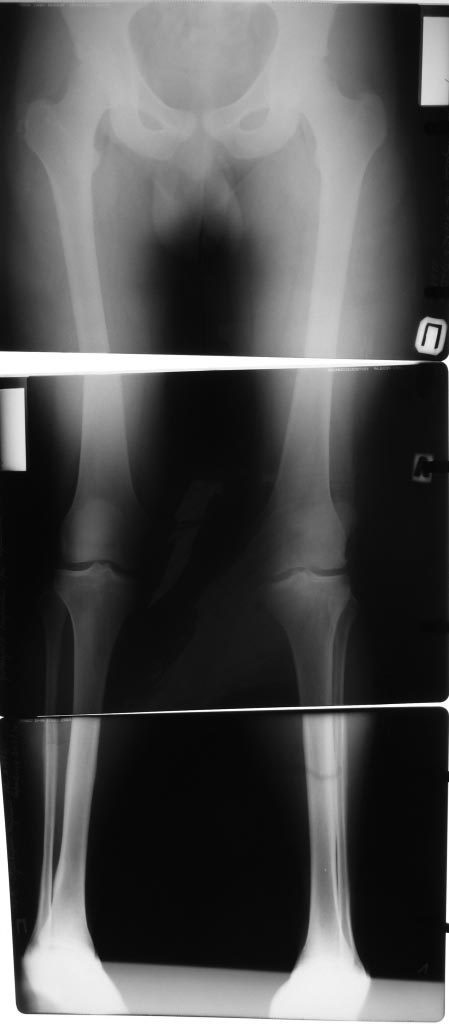

В травматологическом отелеении находится 16 летний юноша с пателло-феморальным артрозом, вторичной деформацией мыщелка бедра и надколенника. Глубокоуважаемые коллеги!Просим вас прокомментировать тактику лечения представляемого больного.Крупный ребёнок 16 лет. Избыточный вес. Не заинтересован в физических нагрузках. Обратился с жалобами на боли в левом коленном суставе при ходьбе. В 2011 году находился на стационарном лечении в нашей кинике по поводу застарелого перелома внутреннего края левого надколенника с разрывом капсулы сустава, хондромаляции наружного мыщелка бедра и гемартроза. За год до госпитализации перенёс двукратный спонтанный вывих левого надколенника. В отделении (март 2011 года) выполнена артроскопия, санация гиалинового хряща наружного мыщелка. Артропластика по Кемпбеллу. Рентгенограммы той поры не сохранились. Через 2 месяца после оперативного лечения ребёнок находился в отделении по поводу послеоперационной-посттравматической разгибательной контрактуры коленного сустава. После выписки больной исчез из поля зрения. Повторно обратился только в настоящее время. При осмотре: Походка не изменена. Вальгусная деформация коленных суставов: справа – 12, слева 15. Движения в коленных суставах в полном объёме. Выпот не определяется. Наружная ротация левой стопы 15-20 градусов. Левый надколенник латеролизован. При сгибании левого коленного сустава происходит наружная дислокация надколенника. Фото больного и результаты рентгенологического обследования прилагаем (будут выкладываться последовательно). Исходя из жалоб и результатов обследования, нами рассматривается следующий вариант хирургической помощи больному. Надмыщелковая остеотомия бедра, выполнение 15 градусов внутренней ротации дистального сегмента, его варизирующее отклонение на 15 град. до исправления вальгуса (анатомической оси конечности ). Очень сомневаемся в отношении вмешательства на поддерживающем аппарате надколенника. Мнения разделились: сделать латеральный релиз , либо не трогать совсем. Делать ли дупликатуру медиального отдела капсулы? Вызывает опасения неконгруентность суставной поверхности надколенника. Рассматриваем вариант V-образной остеотомии надколенника. Следует ли «подгонять» такой надколенник по мыщелку или оставить в надежде на постепенную перестройку. Как одна из ожидаемых проблем после выполнения вмешательства – резкое ограничение сгибания, так как в настоящее время надколенник «уезжает» с мыщелка при сгибании – что, скорее всего, вызвало укорочение квадрицепса и собственной связки надколенника. Может ли появиться необходимость вмешательства на собственной связке и бугристости одномоментно?Больной не настаивает на оперативном лечении. Родители же согласны с необходимостью коррекции. Как один из вариантов – не трогать нам его совсем. Живёт же . Будем благодарны за соображения, подсказки и опыт похожих ситуаций.

На фото этого крупного подростка и снимках видно, что проблема не в отдельно взятом артрозе пателло-феморального сочленения. Отчетливо вида вальгусная установка колена, продольное плоскостопие, значительная торзия бедра кнаружи, очевидна дисплазия латерального надмыщелка бедра. Коррекция одномоментная всего этого вряд ли возможна, да и не рвутся на нее родители.Возможно сейчас можно обойтись малой кровью- эндоскопическим латеральным релизом надколенника, полечить имеющийся ОА гиалуроновой кислотой, заставить носить стельки и сбросить вес.После завершения роста, при наличии клиники ОА, а она непременно будет, возможны и варизующая высокая тибиальная остеотомия и возможна транспозия бугристости. Но вариант удаления надколенника или его остеотомии я бы всерьез не рассматривал- последствия непредсказуемы.

Судя по предсавленным снимкам, у парня ретровесионная деформация шейки бедра, вальгусная деформация бедра, внутренняя ротация голени,гипотрофия наружного мыщелка бедра, возможно высокое стояние надколенника!!!